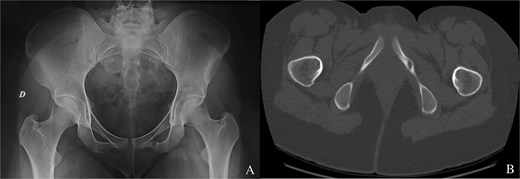

We report the case of a 24-year-old woman with no particular pathological history who complained of buttock pain radiating to the lateral region of the hip and which had been present for 8 months. Most of the pain was nocturnal, resistant to the usual medical analgesic treatment. No spinal or knee symptoms were reported. Clinical examination revealed a well-localized tenderness over the left buttock, corresponding to the ischial region. Mobilization of the hip and knee was painless. Pelvis X-rays showed a millimetric radiolucent area surrounded by an osteosclerosis at the ichiopubic ramus of the left obturator frame (Fig. 1A). The appearance was in favour of an osteoid osteoma. Computed tomography supported the diagnosis (Fig. 1B).

(A) Osteoid osteoma of the left ischiopubic ramus on the anteroposterior view of a pelvic X-ray. (B) Osteoid osteoma of the left ischiopubic ramus on an axial section of the CT scan of the pelvis.